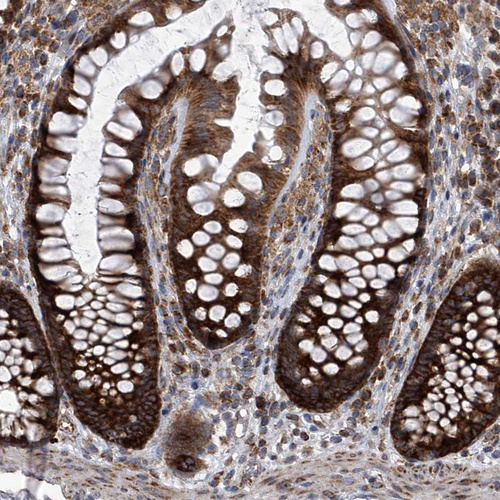

Immunohistochemical staining of human cerebral cortex, gastrointestinal, placenta and testis using Anti-ZC3H15 antibody HPA031099 (A) shows similar protein distribution across tissues to independent antibody HPA031100 (B).